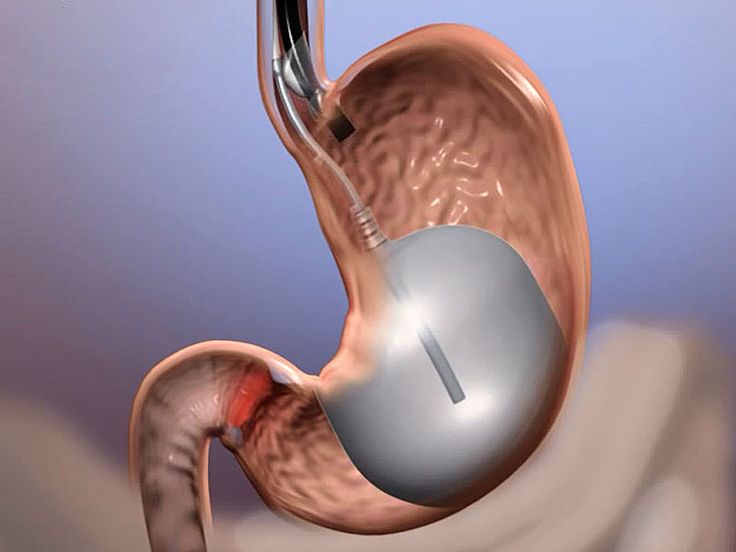

تعد مشكلة زيادة الوزن من التحديات التي يعاني منها الكثيرون، وقد يكون من الصعب إيجاد الحلول الفعّالة التي توفر نتائج طويلة الأمد. في الآونة الأخيرة، أصبح بالون المعدة في الرياض واحدًا من أبرز الحلول المتاحة، لما له من فوائد في مساعدة الأفراد على فقدان...

تعتبر عملية بالون المعدة في الرياض من الخيارات الشائعة للأشخاص الذين يسعون لفقدان الوزن بطريقة غير جراحية. تتيح هذه التقنية للعديد من الأشخاص تحقيق أهدافهم في إنقاص الوزن وتحسين نمط حياتهم الصحي دون الحاجة إلى جراحة معقدة. في هذا المقال، نستعرض تجارب...